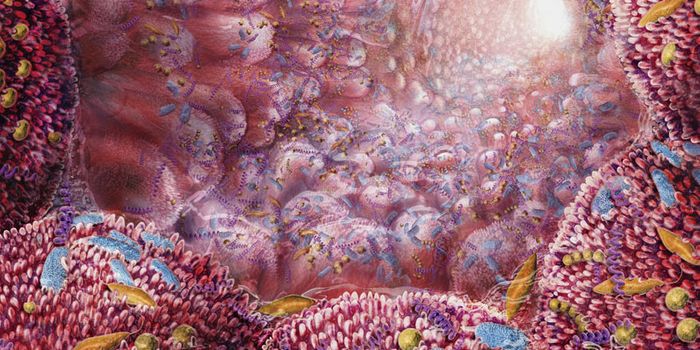

JAN 31, 2017CancerThe importance of the microbiome has only being fully realized and appreciated in the recent years. And nowhere does the ...

APR 13, 2017CancerThe onset of colon cancer may be tied to antibiotic use, reported scientists. The importance of the microbiome has only ...

APR 05, 2017CancerThe composition of microorganisms in a person’s mouth could affect more than just their breath and dental health. ...

AUG 08, 2018MicrobiologyGut bacteria can have a powerful effect on brain function.